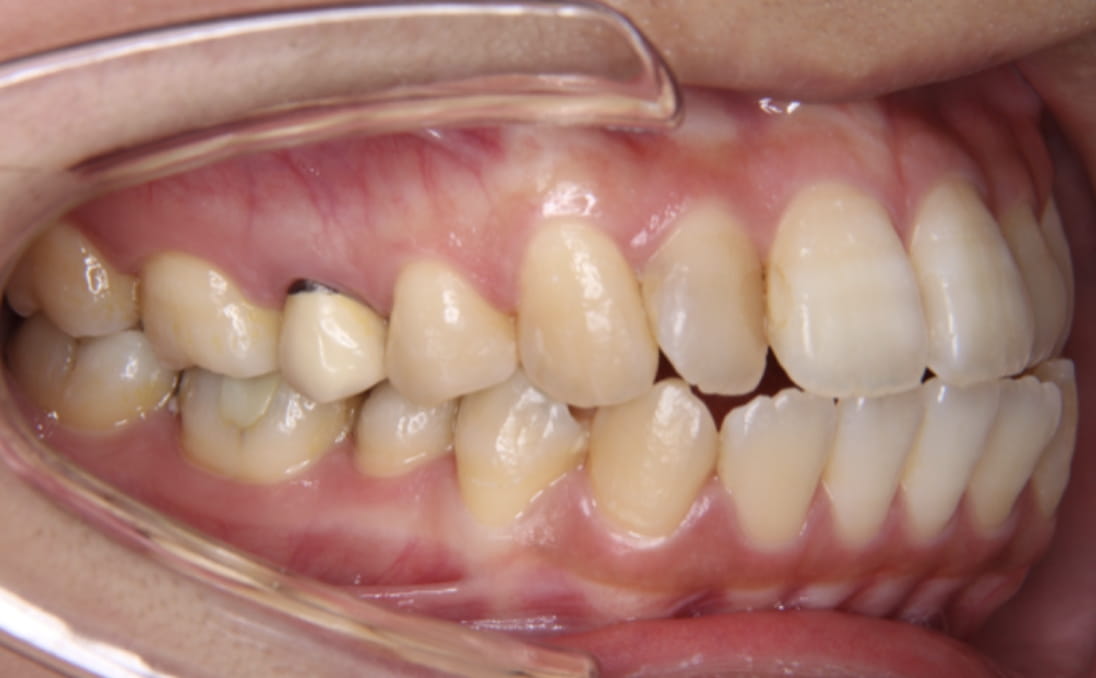

《叢生(デコボコ)を伴う上下顎前突》

症例1

性別:女性 年齢:19歳 お住まいの地域:奈良市

主訴 前歯のガタガタと出っ歯

治療装置 白い表側矯正装置

抜歯 4本の抜歯

治療期間 2年2ヶ月

診断名 歯槽性上下顎前突

副作用 歯肉退縮・歯根吸収・歯髄・壊死・癒着による予期せぬ歯の動き

上下の歯の前歯の角度が傾斜しているため、抜歯が必要なケースでした。

上下の前突感を可能な限り後ろに下げました。

治療前